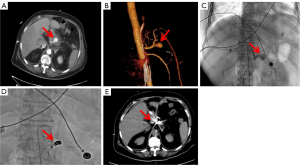

After pancreatic surgery, a pseudoaneurysm in patients was confirmed by CTA. The pancreatic surgeon and interventional surgeon jointly decided to treat the hemorrhage through intravascular intervention. The type of interventional treatment (coil embolization or covered stent placement) was determined by the interventional surgeon depending on the location of the pseudoaneurysm. The clinical course is shown in Figure 1.

Covered stent implantation

For vessels larger than 4 mm in diameter that had inconspicuous tortuosity and supplied vital organs, covered stents were placed. The lesion artery diameter and length were first measured to determine the stent size. If the patient had arterial spasm, preoperative CT was performed to assess the stent size to avoid intimal leakage in type I vessels. The stent covered the proximal and distal ends of the vessel rupture by 1 cm, and other arteries and branches were kept as patent as possible. The diameter of the covered stent was generally 1–2 mm larger than that of the artery. A Mach1 8F guiding catheter (Boston Scientific, Marlborough, MA, USA)—used for a covered stent with a diameter of 5–6 mm—or a Check-Flo 7F long sheath (Cook Medical, Bloomington, IN, USA)—used for a covered stent with a diameter of 7–8 mm—was advanced through the guidewire and pushed to the proximal end of the affected artery. Angiography was performed to confirm the position and ensure no branch occlusion. A 0.018-in guidewire (V-18; Boston Scientific) was used to pass distally to the target artery, and the Viabahn covered stent system (W. L. Gore & Associates, Newark, DE, USA) was placed via a 0.018-in guidewire exchange. Covered stents were 25 or 50 mm in length and ranged from 5 to 8 mm in diameter. Repeat angiography was performed to confirm the exclusion of a pseudoaneurysm (Figure 2). After stent implantation, low-molecular-weight heparin anticoagulant therapy (0.4 mL/4,100 IU; S.C. Q12H) was generally started when the patient’s blood pressure and hemoglobin level became stable. Long-term oral aspirin [100 mg per os (PO) daily] and clopidogrel (75 mg PO daily) antiplatelet therapy was implemented in all surviving patients.

25 mm covered stent was implanted at the lesion site. (D) The contrast catheter was withdrawn to the starting point of the superior mesenteric artery. Re-contrast imaging showed that the stent was unobstructed, and no contrast agent overflow was observed. A follow-up CT scan showed that the covered stent was in place, and there was no narrowing 1 month (E) or 6 months (F) after the implantation of the covered stent. The red arrows respectively represent the positions of pseudoaneurysm and covered stent. CT, computed tomography; CTA, computed tomography angiography.

Coil embolization

Embolization was applied to treat vessels with a small diameter (typically <4 mm), those with a course too tortuous or angular, and those not supplying blood to vital organs. Furthermore, for the bleeding in small arterial branches or vascular stumps that could be treated with covered stents, coil embolization was applied. A microcatheter (STC18; Boston Scientific) was placed in the lumen of the pseudoaneurysm, and contrast agent extravasation was observed on angiography. Microcoils (IDC; Boston Scientific) were used to embolize the inflow and outflow paths of the parent artery. Repeat angiography after embolization showed no extravasation of contrast medium (Figure 3).